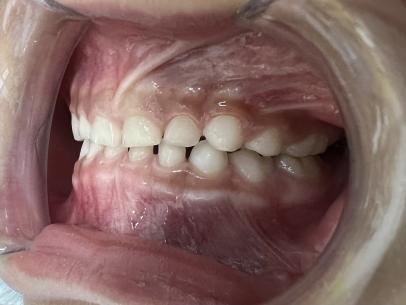

案例一:

治疗前